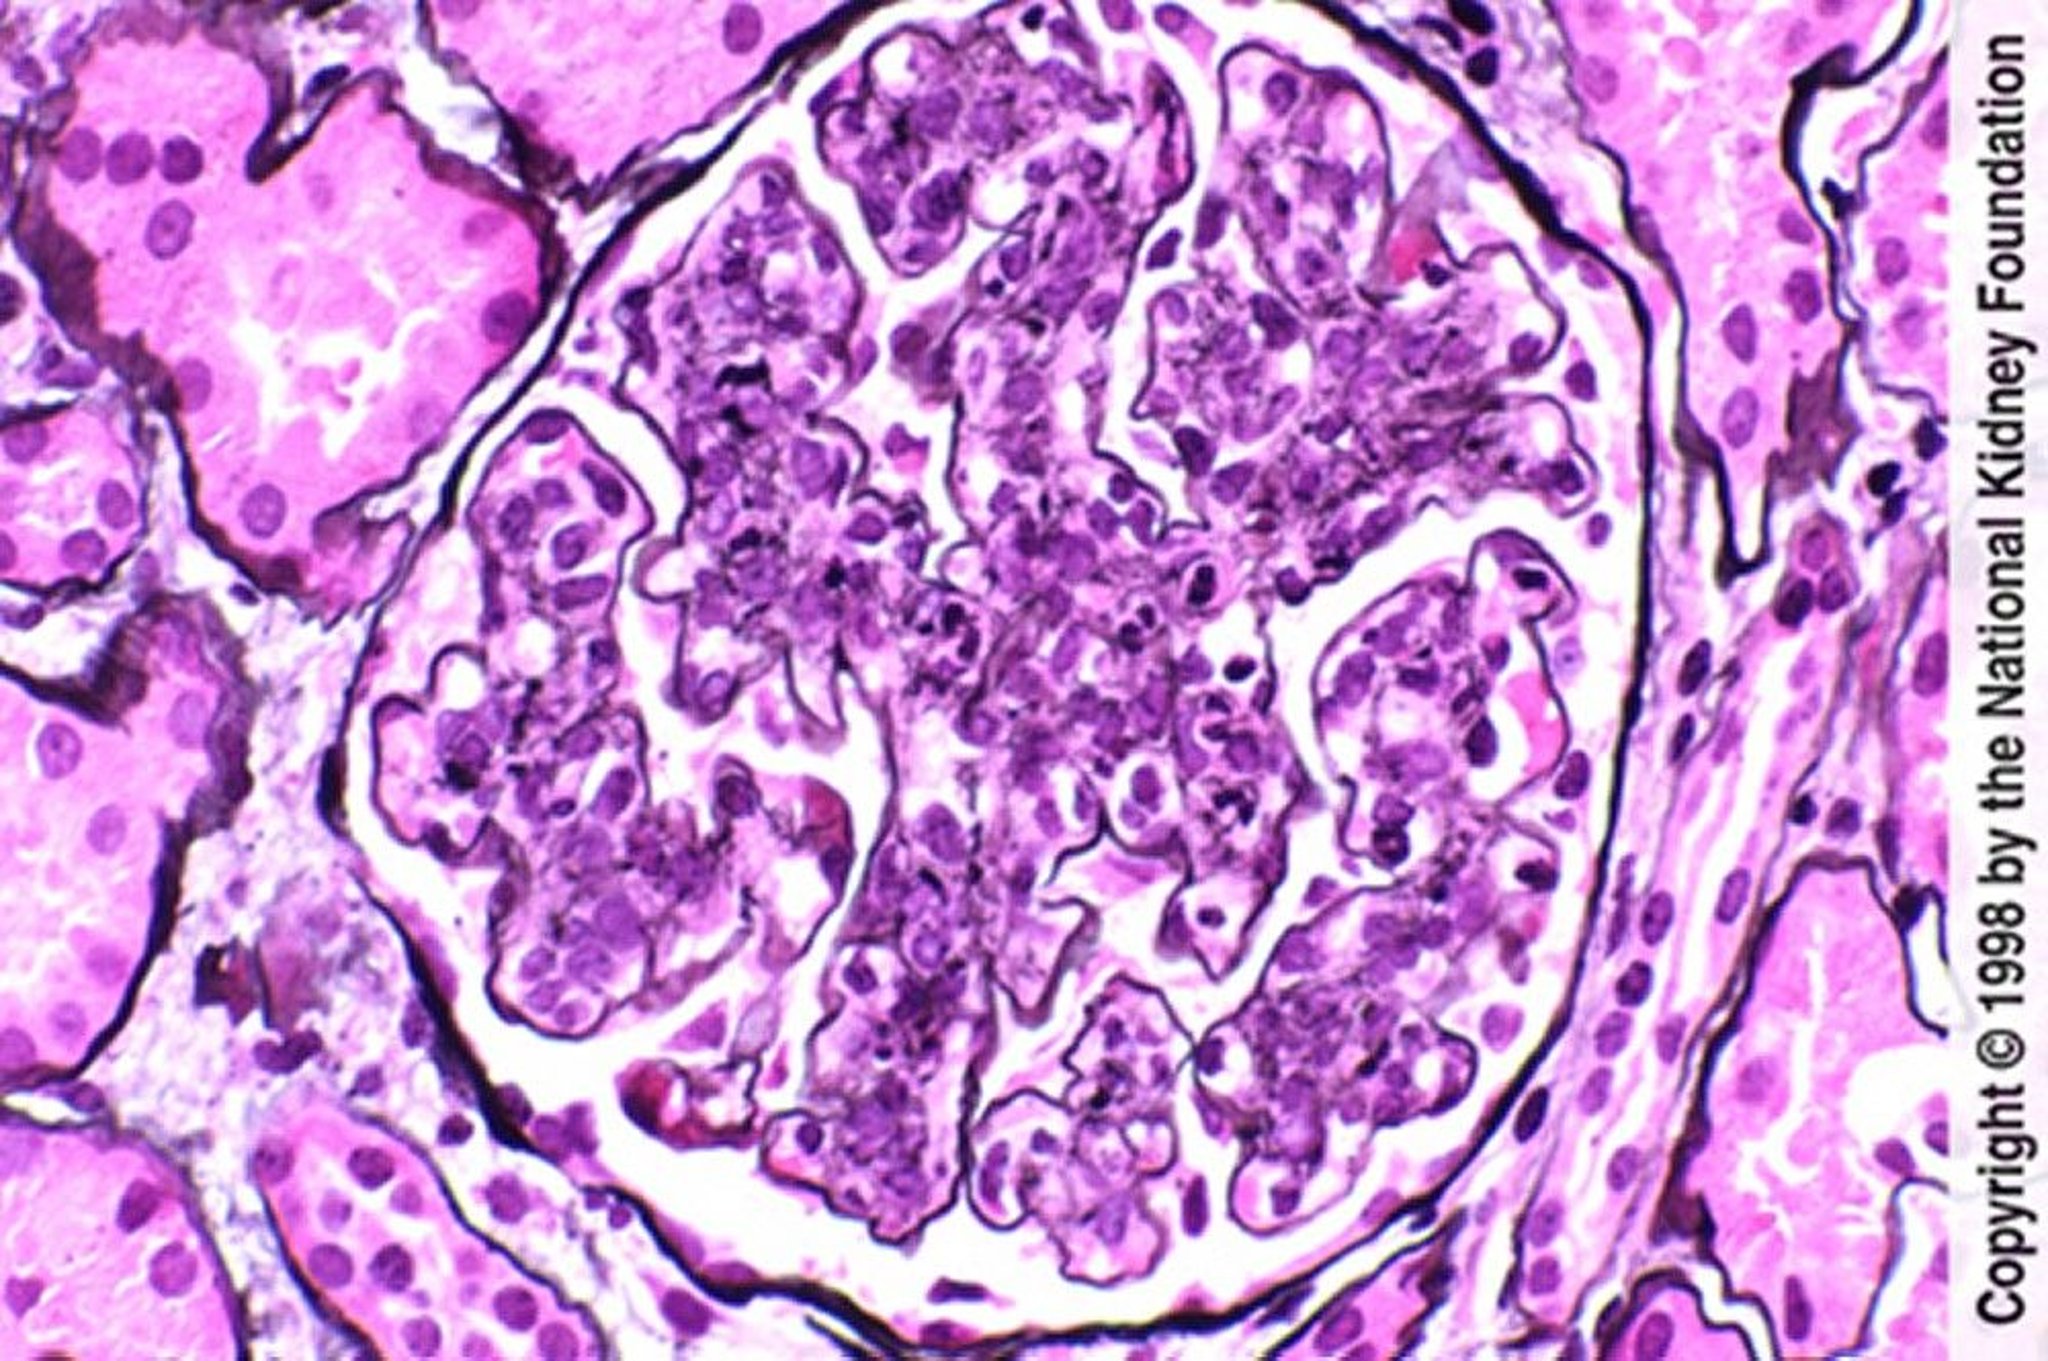

Postinfectious Glomerulonephritis (Hypercellularity With Neutrophilic Infiltration)

Endothelial and mesangial hypercellularity with neutrophilic infiltration (Jones silver stain, ×400).

Image provided by Agnes Fogo, MD, and the American Journal of Kidney Diseases' Atlas of Renal Pathology (see www.ajkd.org).